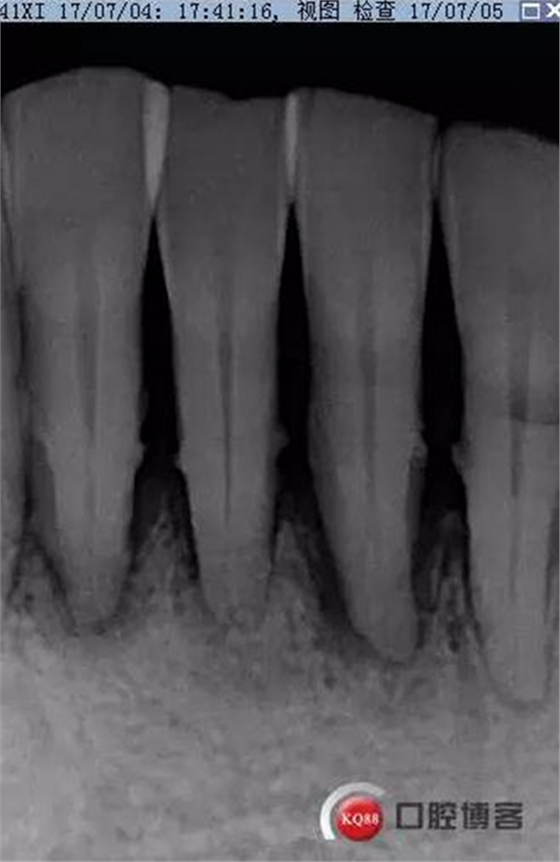

X線(xiàn)示牙槽骨吸收,下頜前牙區(qū)可見(jiàn)齦下牙石影像,牙槽骨吸收至根尖1/3,根周透射影像。

2017-07-05

口腔宣教,全口齦上潔治,齦下超聲刮治,手工根面平整。雙氧水沖洗止血。指導(dǎo)刷牙方式。囑衛(wèi)生維護(hù),一周復(fù)診。

事后再次查看術(shù)前片,可以看到兩個(gè)根管影像,忽略了。